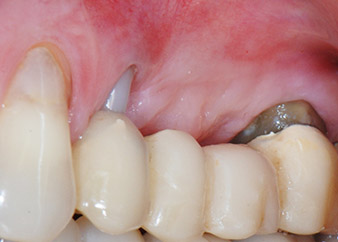

Risultati intermedi dopo due mesi

Le figure 17 e 18 mostrano il risultato clinico due mesi dopo l'intervento chirurgico. Il dente 24 mostra mobilità ridotta di classe 1 secondo Miller e i tessuti molli sono privi di infiammazione. A questo punto l'utilizzo della sonda è stato evitato per impedire una nuova infezione e per non disturbare l'attacco epiteliale. Era stata programmata una visita di controllo al rientro e il posizionamento dei perni di guarigione sei mesi dopo l'inserimento degli impianti.